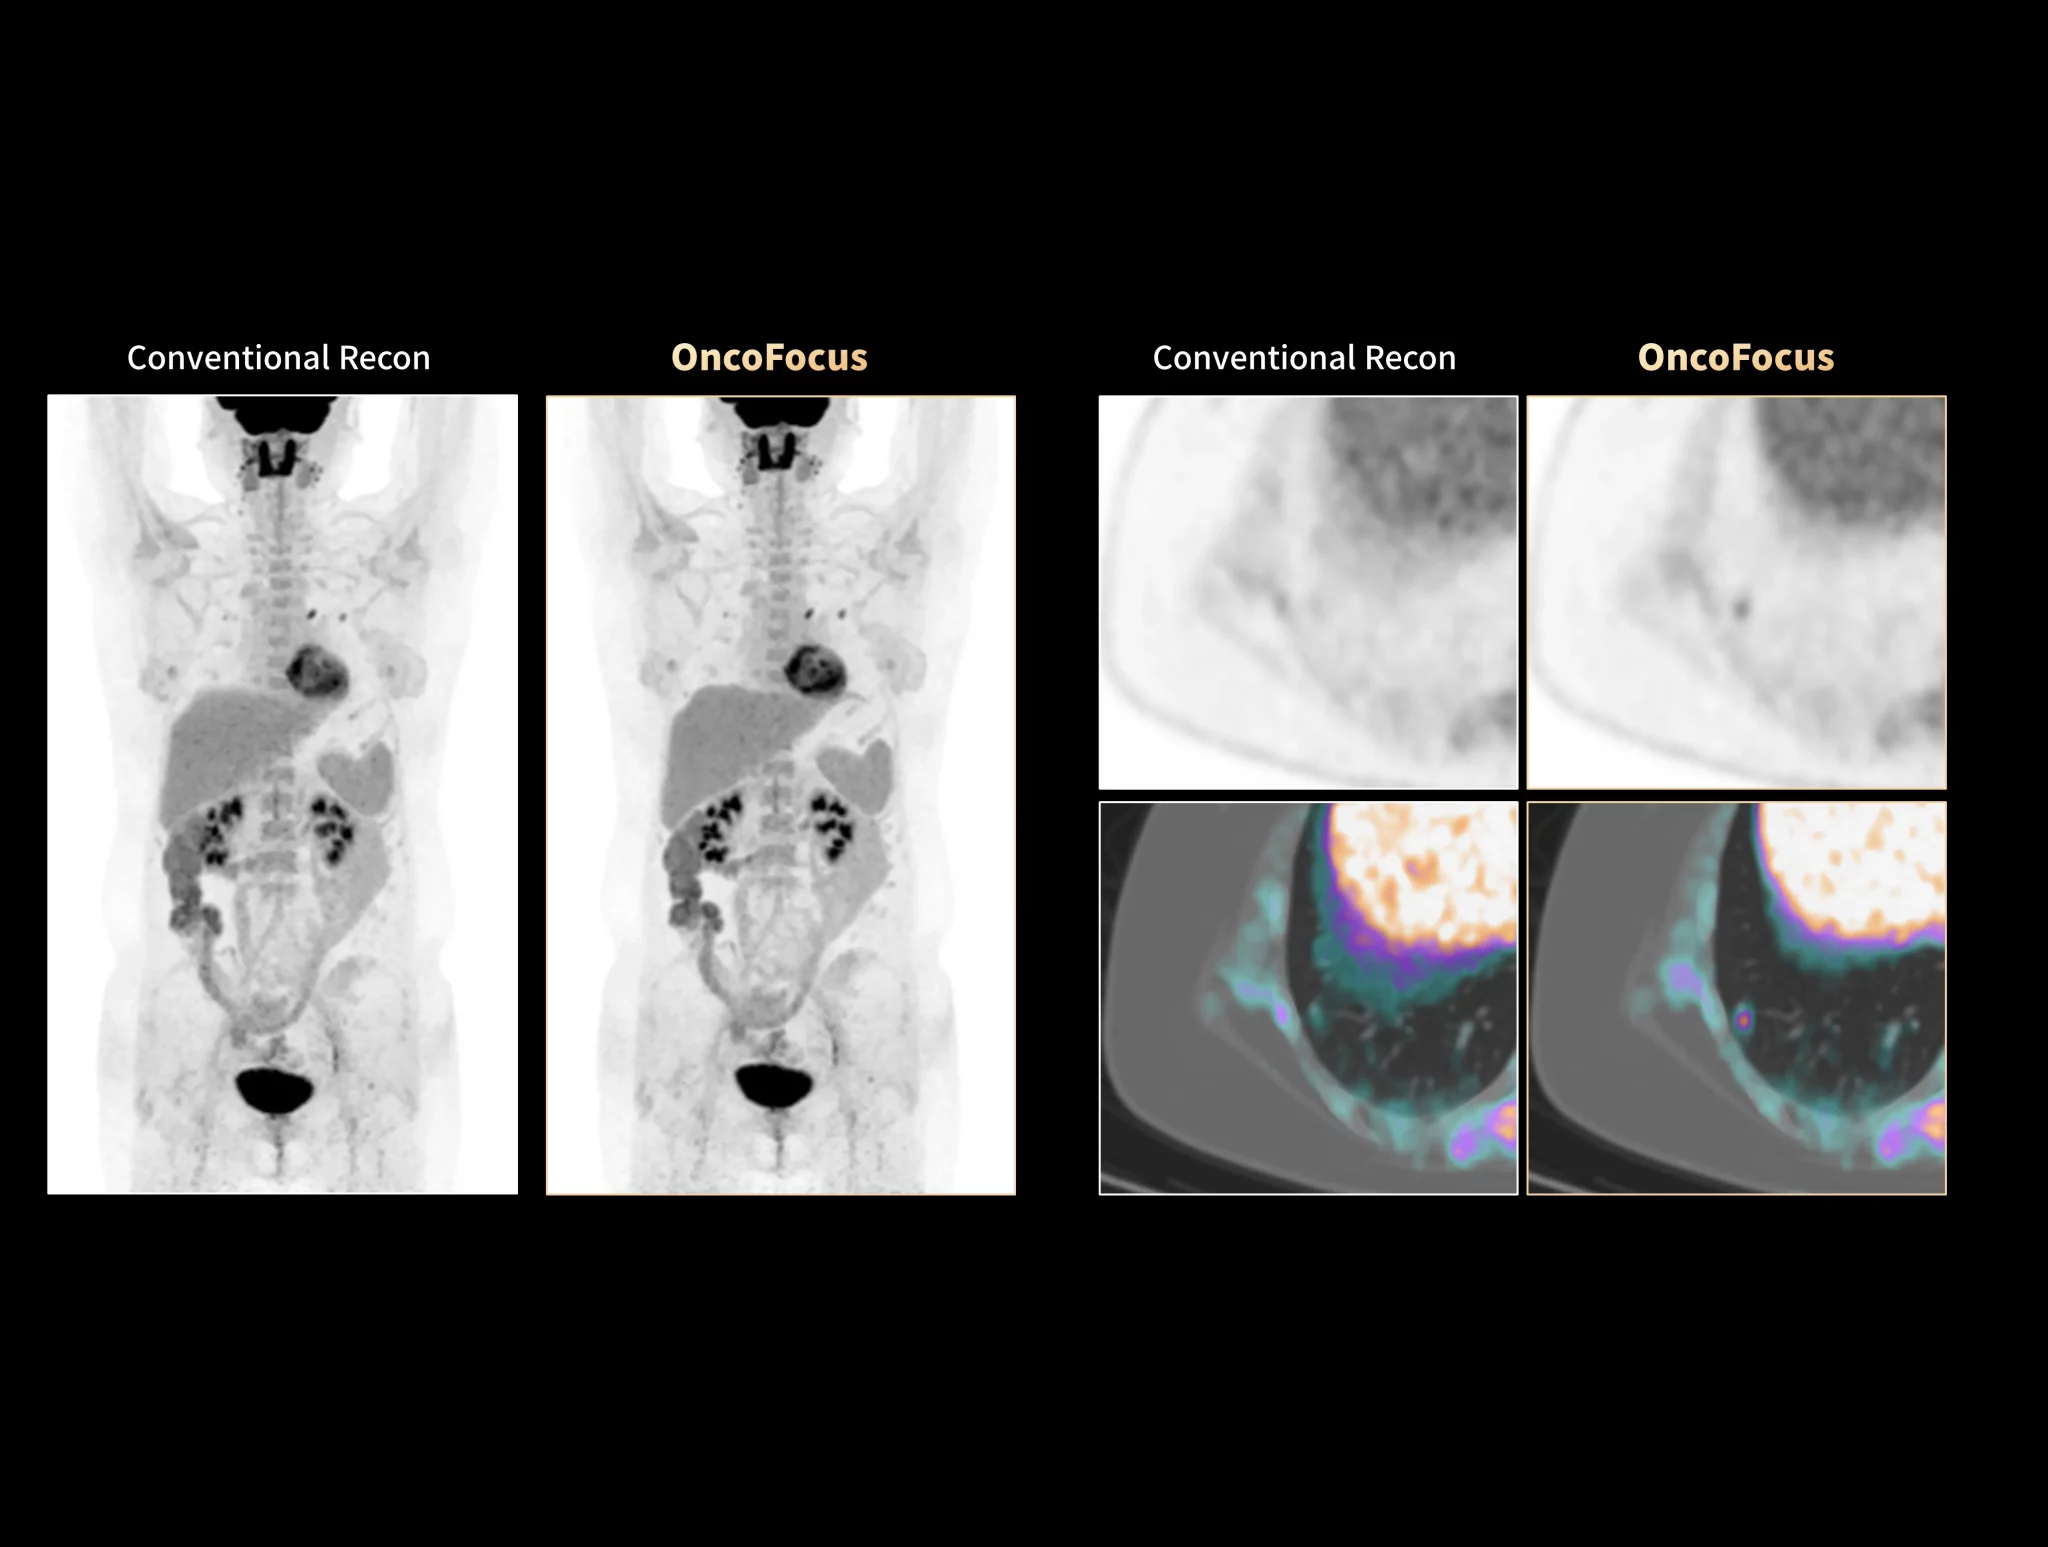

uMI Panorama is greatly empowered by innovative technologies integrated into the uExcel SCAN and uExcel CARE workflows. With uExcel SCAN, you can rely on intelligent positioning, scanning, and motion correction to streamline your routine tasks and maximinze your work efficiency. And uExcel CARE features uExcel DPR and uExcel AIIR reconstruction algorithms to ensure clear images even at low doses.

Unlock New Possibilities for Exploration

With the ultra-high system performance, uMI Panorama faces up to the challenges of tracers with different half lives and the complex scanning conditions, without compromise for image quality.